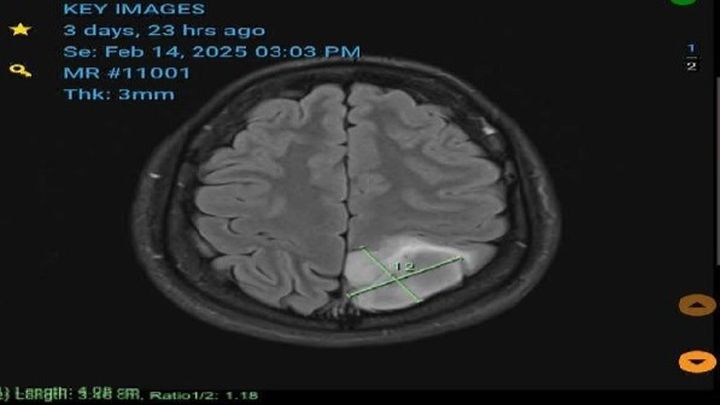

On the 17th of February, 2025. Our dear family member received horrible news that they had a 4x3.4cm tumour on their brain (Visible in the picture of this go fund me). This testing was the result of multiple health complications presented over the last couple of years. And most recently the recipient suffered seizures as a result of this tumour present on their brain.